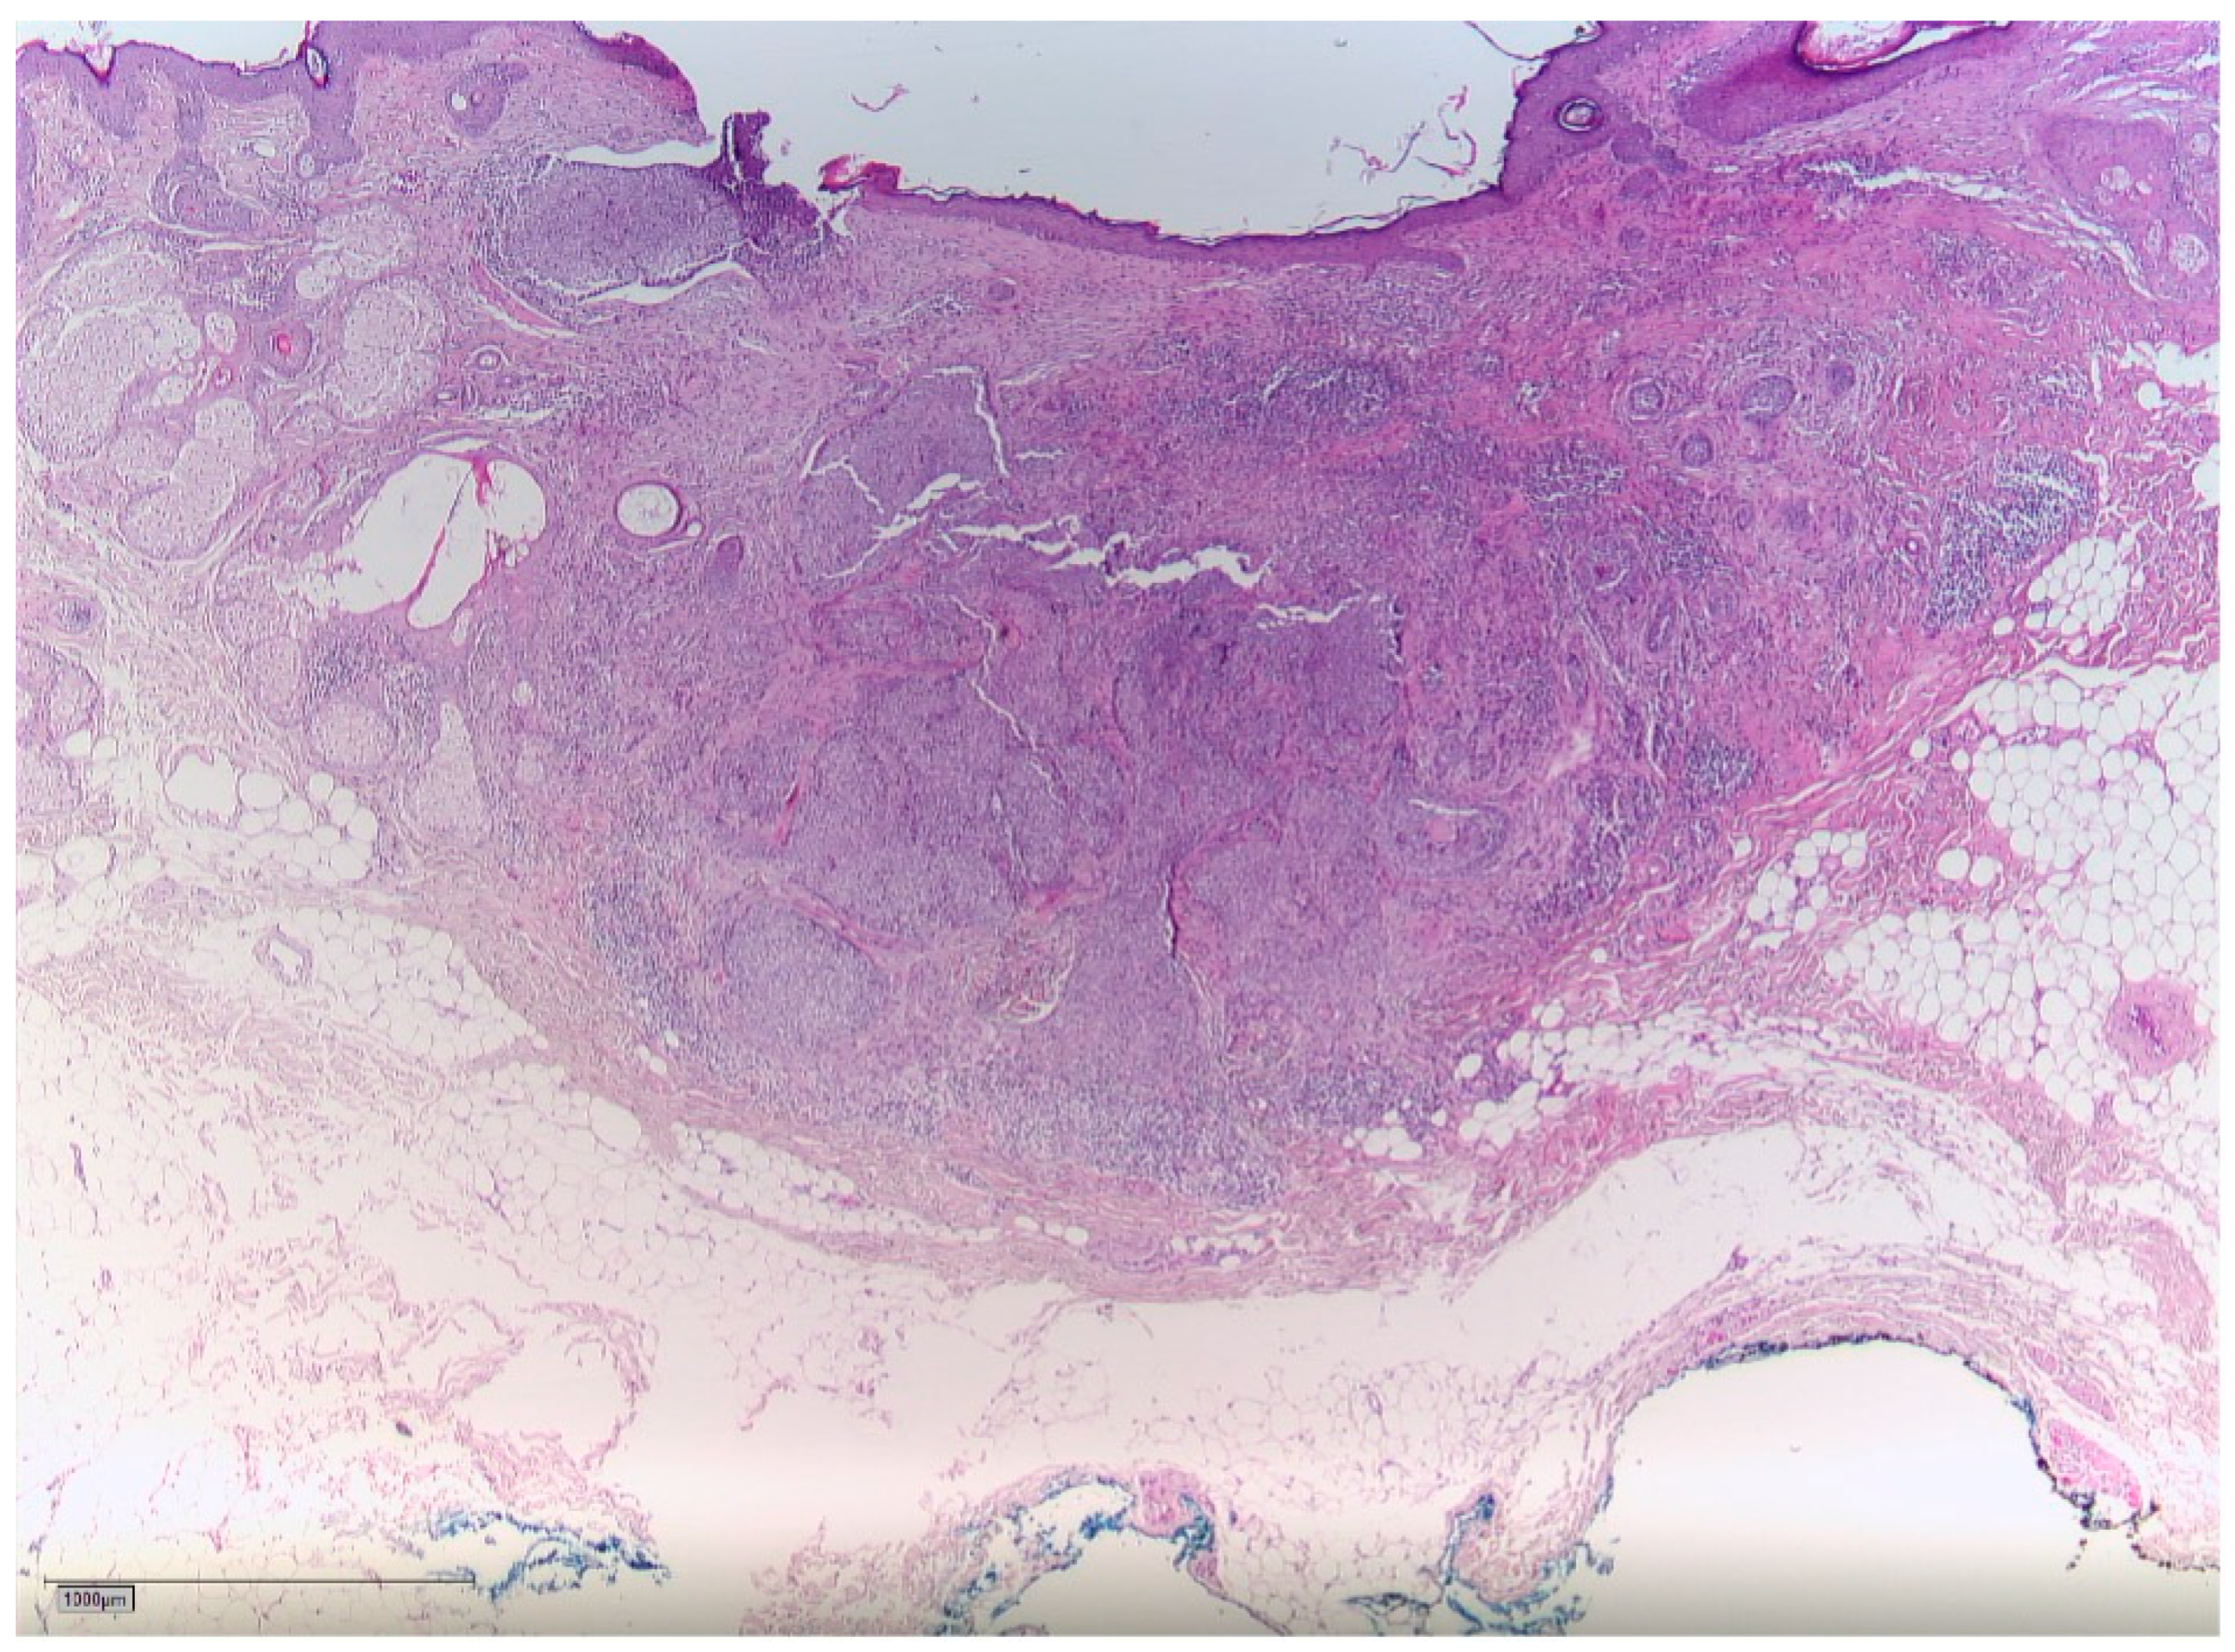

2. Case Report